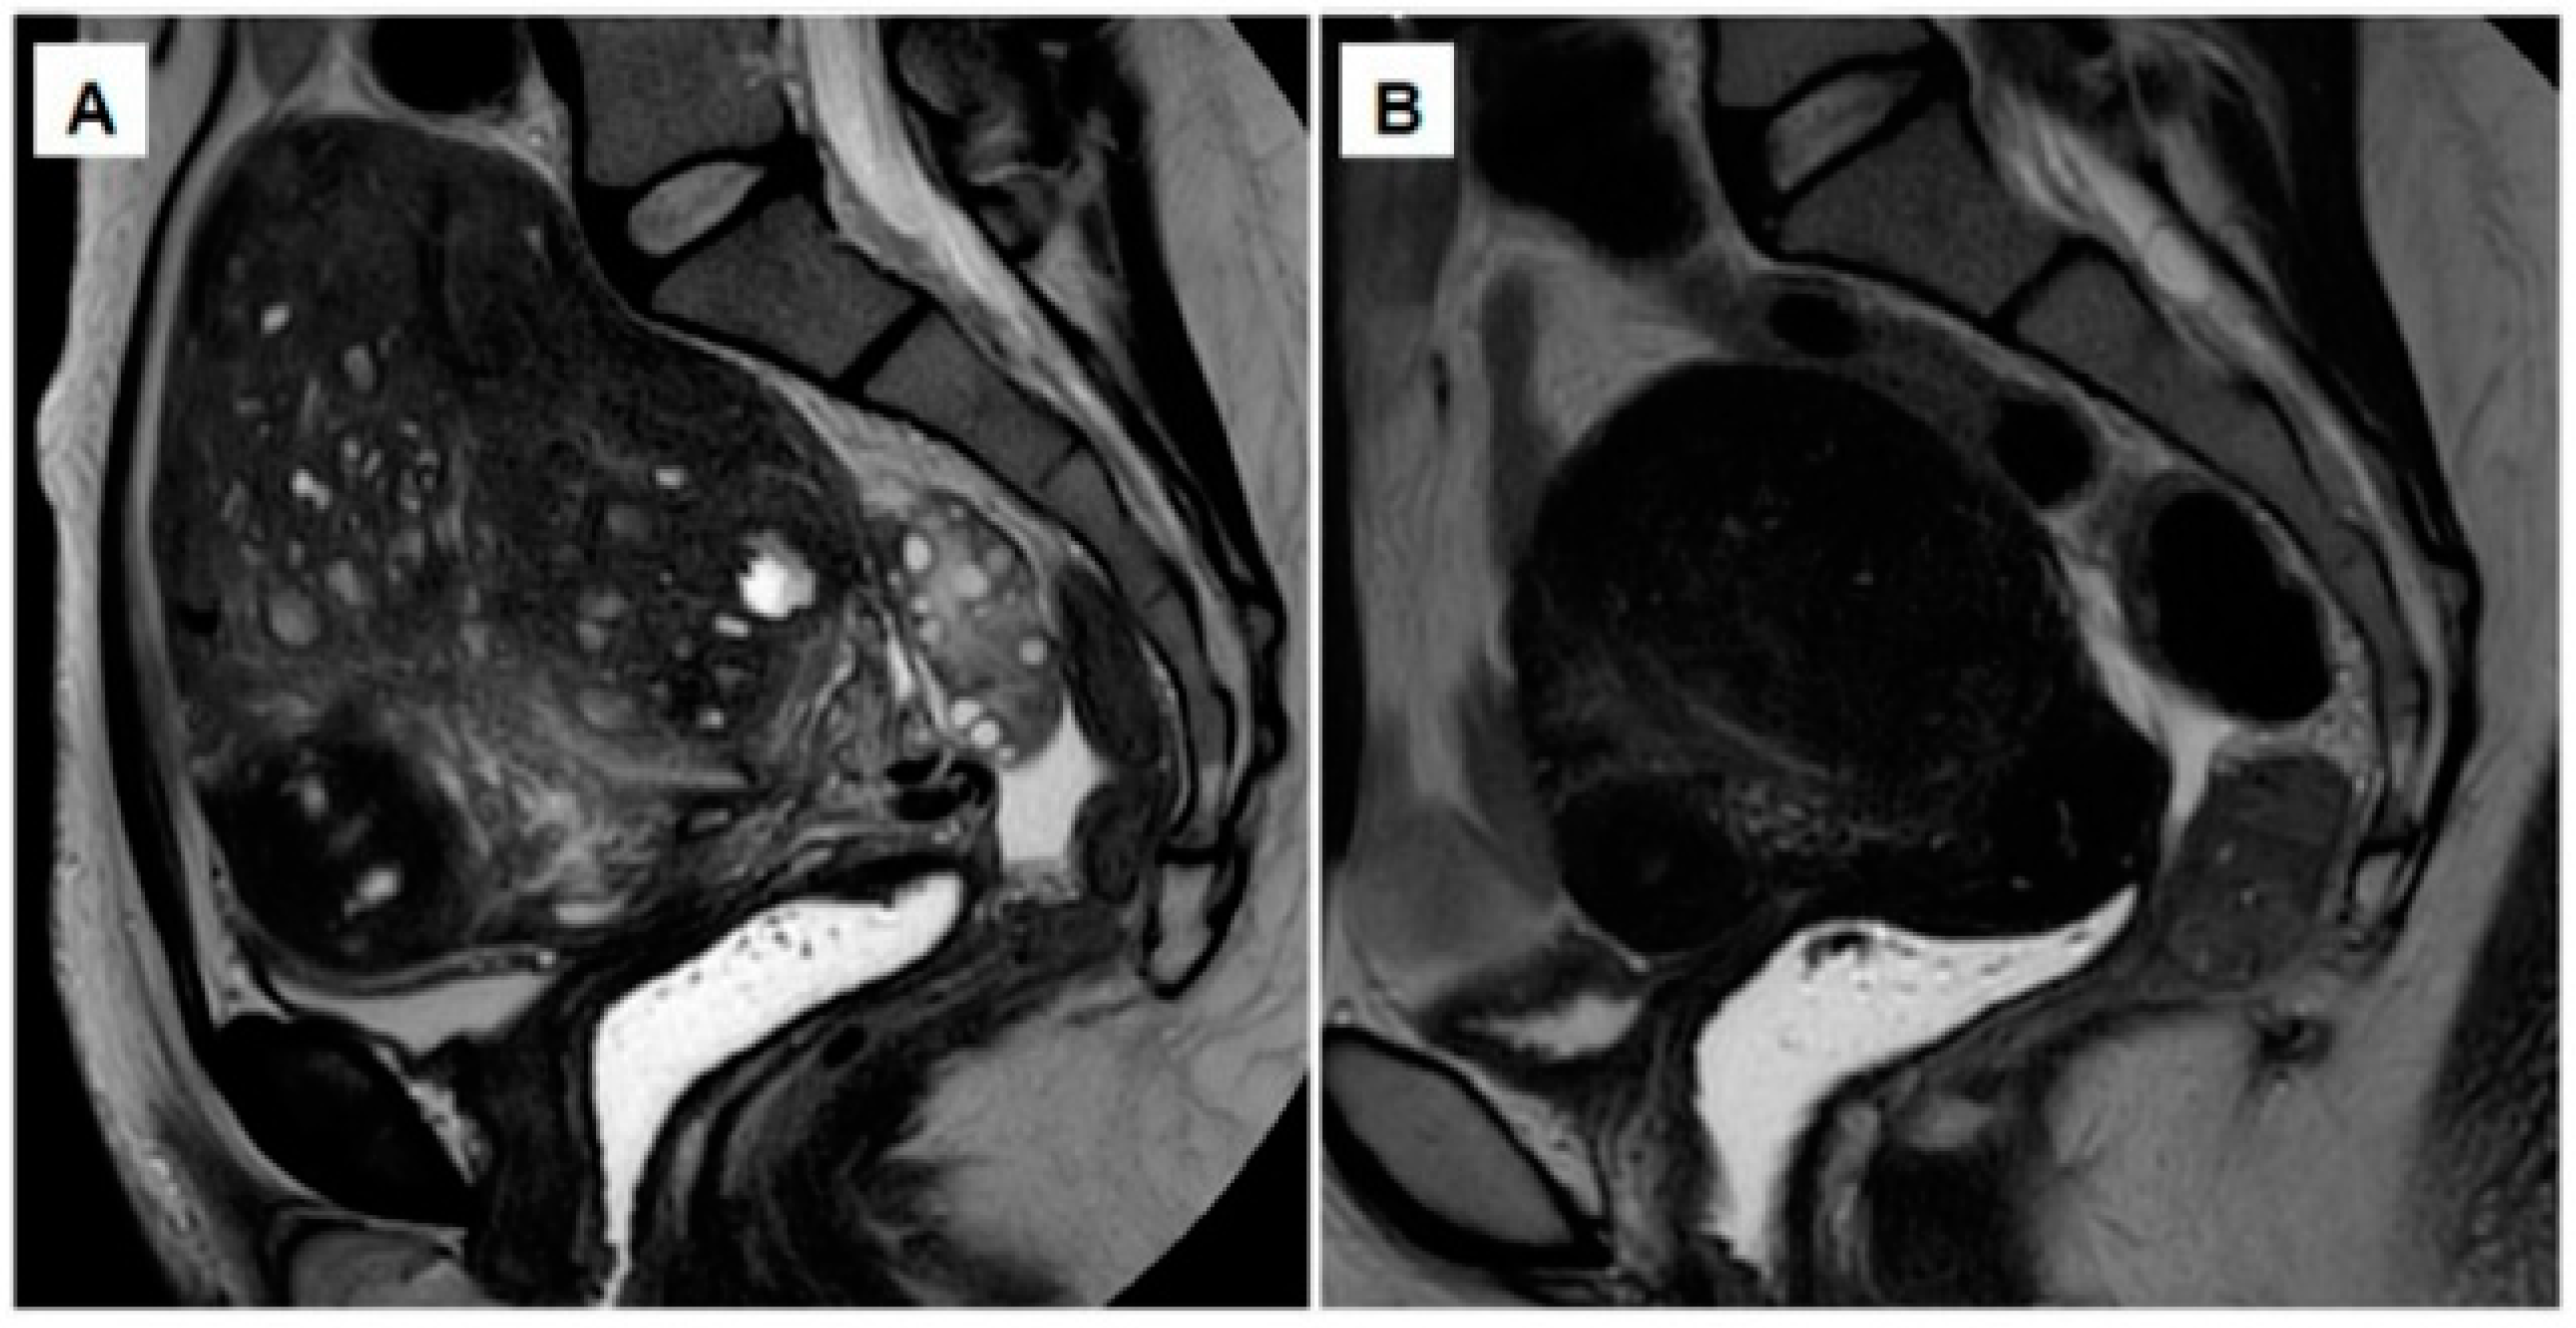

From www.researchgate.net

MR imaging showing significantly enlarged uterus with a heterogeneous... Download Scientific Can An Enlarged Uterus Shrink This can happen for a. Fibroids can actually shrink or grow over time. If your uterus in enlarged because of pregnancy, it will naturally begin to shrink after you deliver. After all, the uterus is capable of expanding to nearly the size of a watermelon in. By one week postpartum, your uterus will be reduced to half its size. Having. Can An Enlarged Uterus Shrink.

From pubs.rsna.org

Diffusely Enlarged Uterus Evaluation with MR Imaging RadioGraphics Can An Enlarged Uterus Shrink Adenomyosis is a condition in which tissue that normally lines the uterus. Having an enlarged uterus isn’t always problematic. After menopause, they often shrink naturally and cause no symptoms. If your uterus in enlarged because of pregnancy, it will naturally begin to shrink after you deliver. For fibroids that are larger or more. Fibroids can actually shrink or grow over. Can An Enlarged Uterus Shrink.